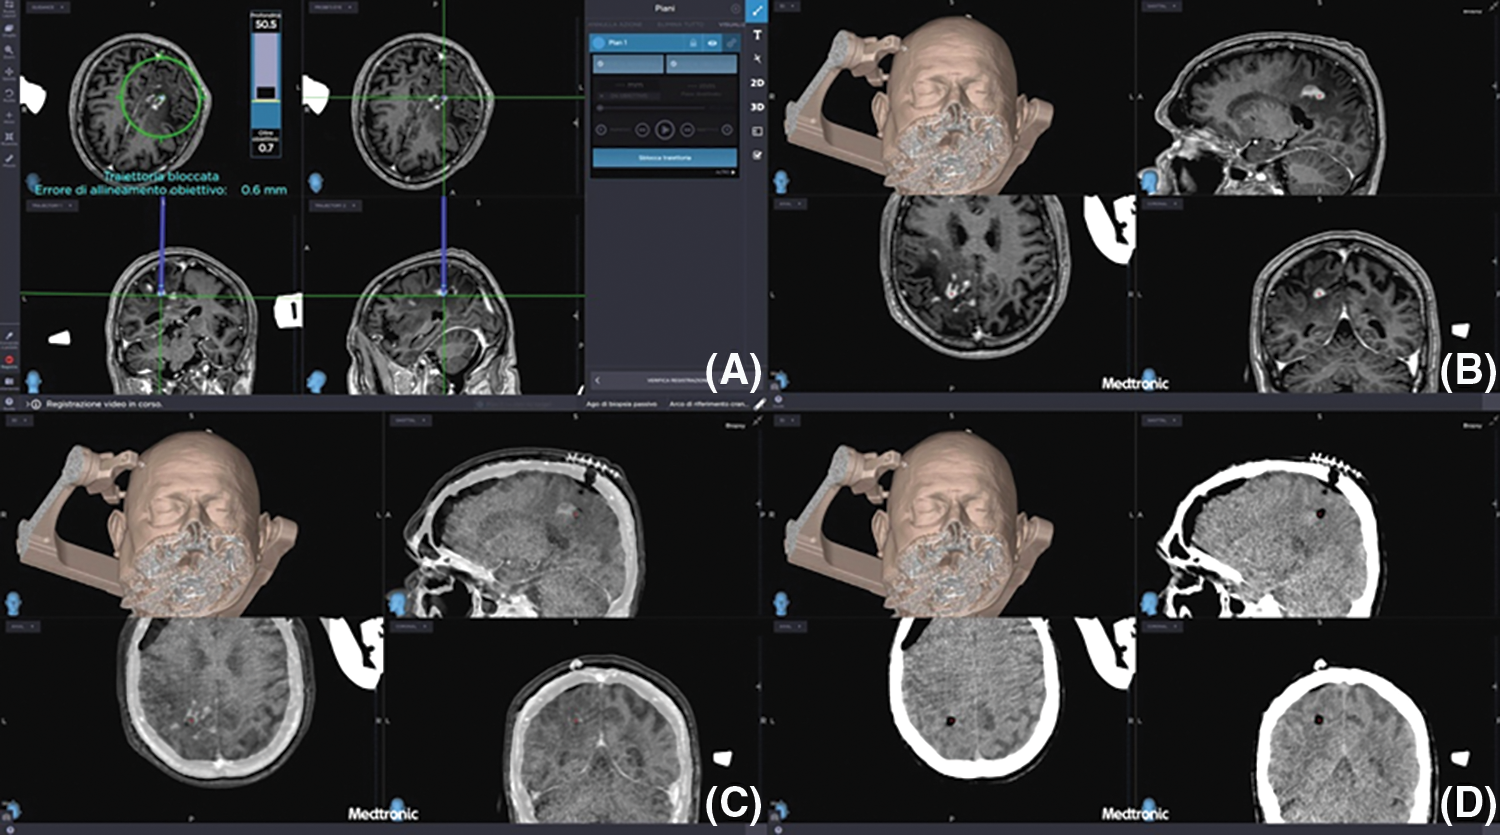

i-CT scan after biopsies confirmed sampling accuracy and excluded procedural complications in all cases (Fig. 5).

Figure 5: (A–D) Preoperative planning of biopsies (upper left image) and preoperative MRI merged with i-CT after biopsies confirming the correct target and the absence of early post-operative complications